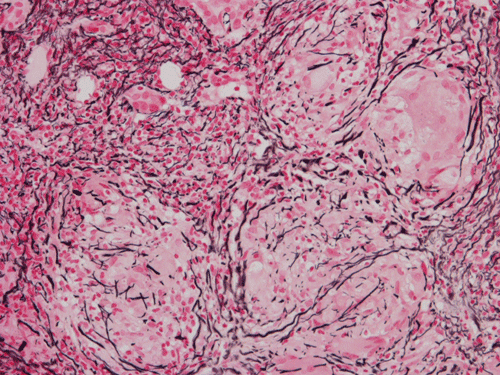

Pathology of the Case: At low magnification, a few small nodules (arrow in Panel A) can be seen with the hematoxylin and eosin stained section. On medium magnification, these nodules correspond to sharply defined granuloma without necrosis. These granuloma are not associated with a high density of lymphocytes in the surrounding liver parenchyma (Panel B and C). Multinucleated giant cells (arrow in Panel C, magnified in Panel D). On reticulin stain, there are reticulin fibers that extends into the granuloma (Panel E). Trichrome stain demonstrated bridging fibrosis (Panel F). The granuloma are well defined and some of them are surrounded by fibrous tissue (Panel G). Immunohistochemistry demonstrated preservation of bile ductules as well as proliferation of ductules (Panle H). No residual ductules are noted in the granuloma as revealed by immunohistochemistry for CK7 (Panel I). Neither acid fast bacilli or fungal organisms are identified by acid fast stain and Gomori's methenamine silver (GMS) stain.

Histopathologic features of sarcoidosis include scattered granulomas in the liver, which may tend to be portal or periportal. Multinucleated giant cells, epithelioid cells, and a variable but usually minimal inflammatory cellular response is present. The granulomas, like in sarcoidosis occuring in other organ systems, tend to be well-demarcated or "clear cut", several granulomas are often comparable in size, and necrosis is not typically present. Asteroid bodies, intracellular vacuolated structures resembling a sea anemone, may be found within the giant cells. Large basophilic, round to roughly oval, and concentrically laminated, Schaumann bodies may be evident in the sarcoid granuloma. None of these inclusions are pathognomonic feature of sarcoidosis, however, do suggest this diagnosis. Ductopenia, cholestasis and features of chronic cholestasis resembling PBC have been described in the cases of sarcoidosis. Severe fibrosis and cirrhosis in conjunction with portal hypertension may be present in sarcoidosis. End stage liver disease in sarcoidosis has been successfully treated by orthotopic liver transplant and recurrent disease has been reported in one such case. Reticulin fibers has a tendency to extend into the granulomas as illustrated in this case.